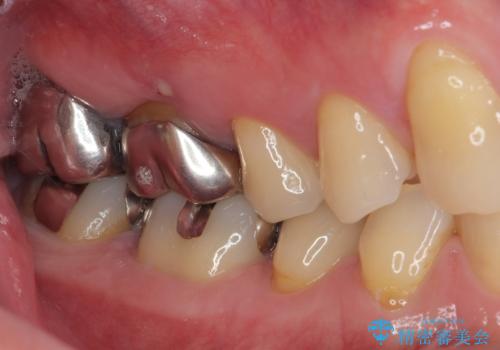

拡大鏡視野下で虫歯を除去しオールセラミッククラウンに適した形に整えました。

歯と歯茎の間に圧排糸と言われる糸を入れてシリコーン印象材にて型どりをしました。

審美面、機能面共に満足していただけました。

順次、後ろにある不適合のメタルインレーの部位をやり替えていく予定です。